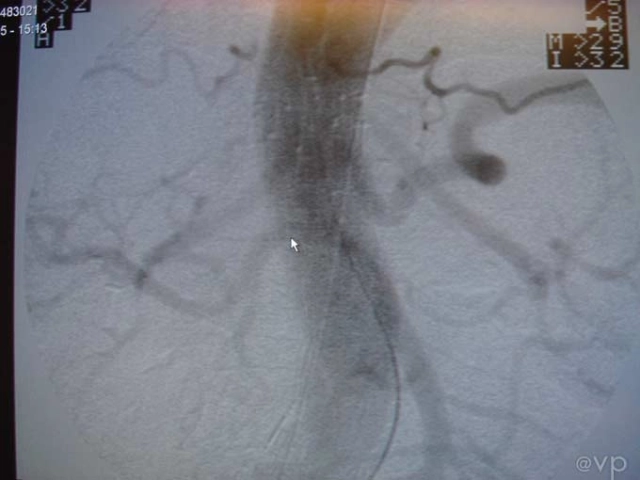

Intestinal